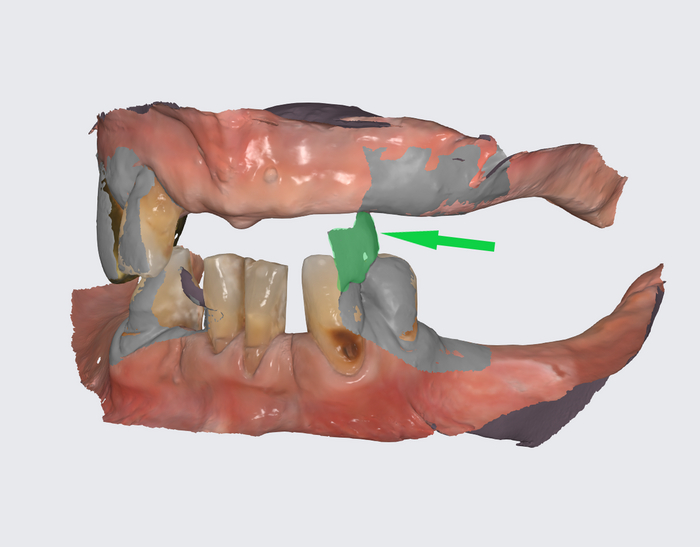

Вот как выглядит цифровая принтованная постановка:

Цифровая принтованная постановка

Разница - в первом варианте зубы не из стандартного набора, а те, что пациенту подходят больше. С этим прототипом можно даже пожить какое-то время, попривыкать к нему. Понять, что нравится, а что не особо.

И так всё затянуто. Но то зуб на зуб не попадает, то губы не смыкаются: